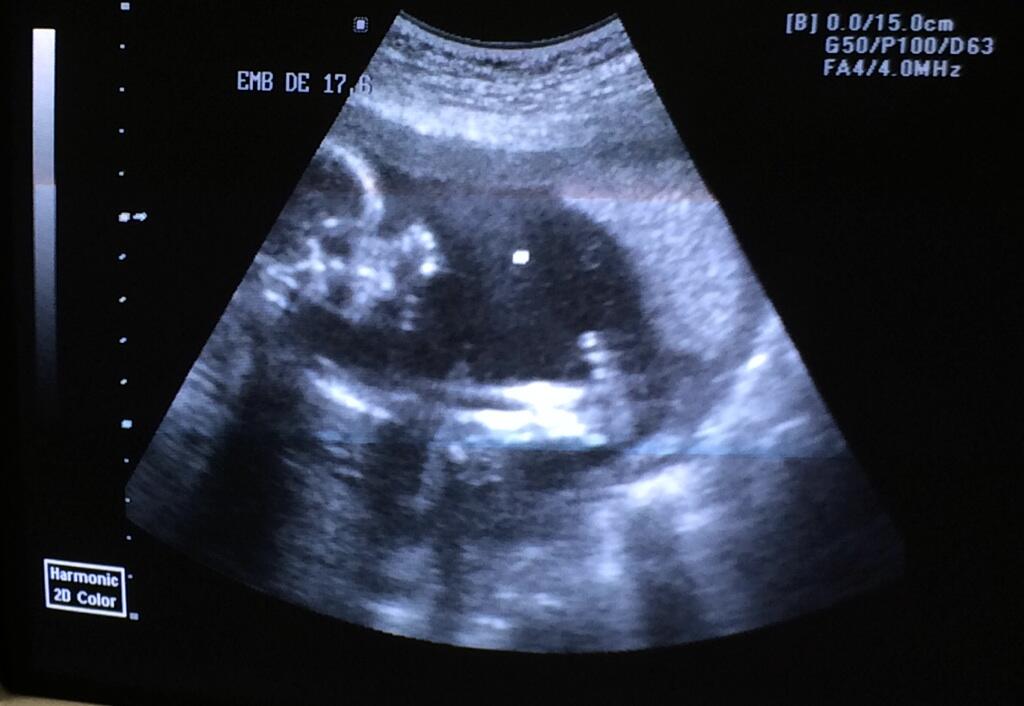

Mehiški igralec Rodrigo Abed je na svojem twitterju objavil spodnjo sliko, ter da je presrečen, da bo ponovno postal očka, hkrati pa se je še zahvalil Bogu za takšen blagoslov. Rodrigo je leta 2009 prvič postal očka deklici Elisi, dve leti kasneje pa je dobil sina Aarona.